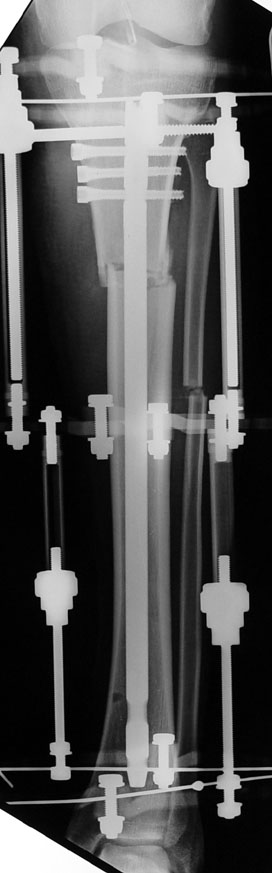

3. POSTTRAUMATIC LOWER LIMB SHORTNESS (MALUNION)

This type of shortness occurs after a fracture heals in a shortened position. Most cases are seen in adults and can be treated with one lengthening operation. Additional deformities can be corrected simultaneously. Most of these cases can be treated with lengthening over nail or just corrections and intramedullary nailing.